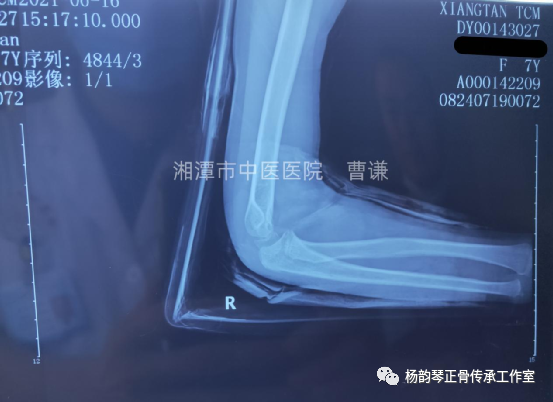

入院后予以手法复位,小夹板外固定,拍片复查示骨折对位对线良好,桡骨头脱位已纠正。具体复位手法:术者一手拇指先摸清桡骨头位置,将拇指置于肘前方,然后另一手握前臂置于前臂旋后位,再极度屈肘,拇指卡于肱骨与桡骨之间形成杠杆,通过极度屈肘促使桡骨头复位。用锐角托板固定于患肢屈肘60°(邻肢夹角法)前臂旋后位。

伤后半月余复查骨折对位对线良好,肱桡关节匹配良好,改直角托板固定,每次换药进行被动肘关节屈伸锻炼,这样有利于促进关节功能早期恢复。

伤后近一月拍片复查骨折愈合良好,肱桡关节匹配正常。